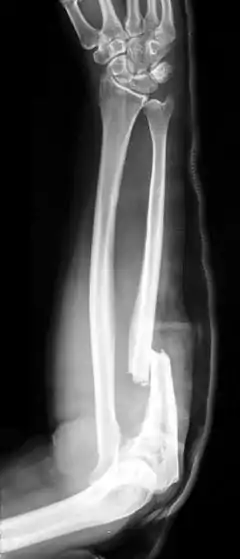

| Monteggia Fracture (type of ulna fracture) | |

- Monteggia fracture - a fracture of the near to elbow end of the ulna with the dislocation of the head of the radius at the elbow joint.[2]

Monteggia Fracture (fracture of proximal ulna)